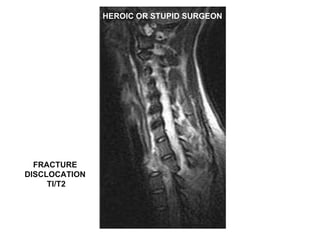

HEROIC OR STUPID SURGEON FRACTURE  DISCLOCATION  TI/T2

Results  MRI scans in all patients Early operation in majority No intra-operative complications Safe operations with minimum equipment 2 patients were irreducible